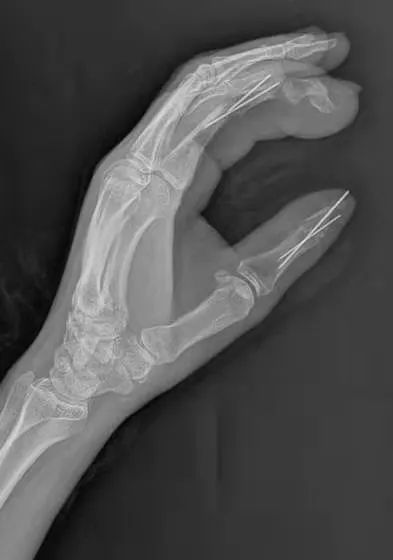

下午三点半,手术开始,在臂丛+腰硬联合麻醉下行左手清创,左拇指再植;通过改良左足踇甲瓣与第二趾趾骨共蒂嵌套重建左示指。

术前、术中照